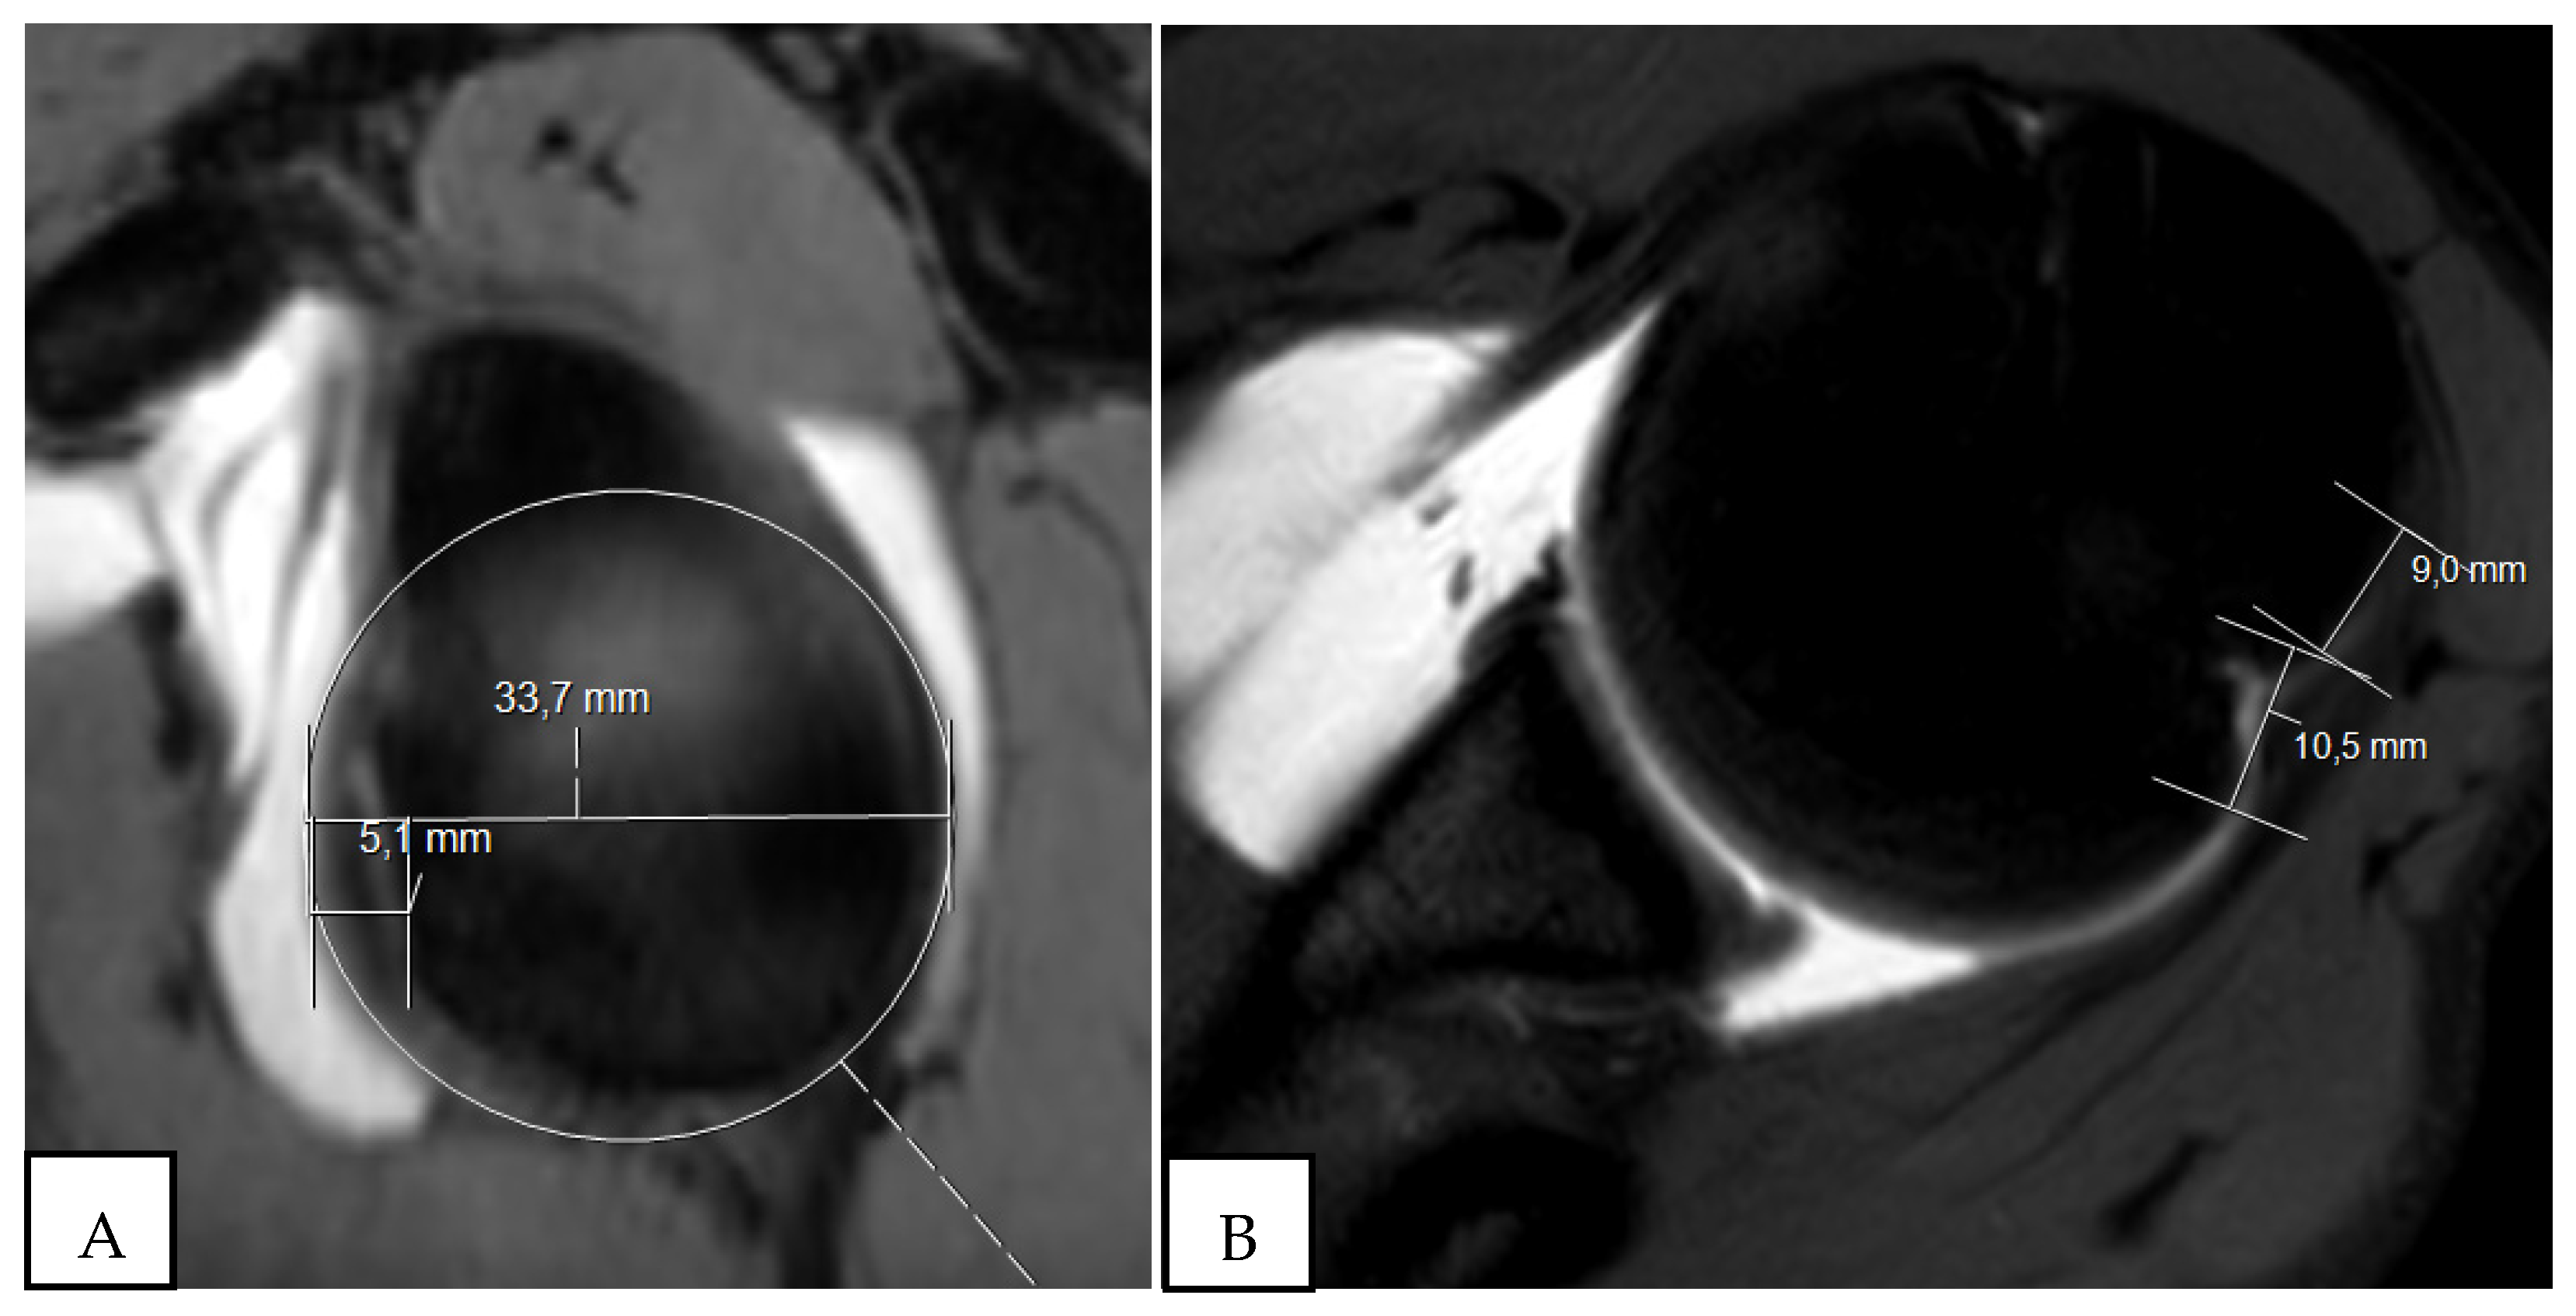

2. The Glenoid Track and Hill–Sachs Lesions: On-Track and Off-Track